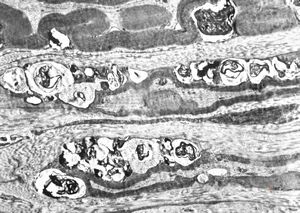

M, 2y. | globoid leukodystrophy (Krabbe disease) … n. suralis